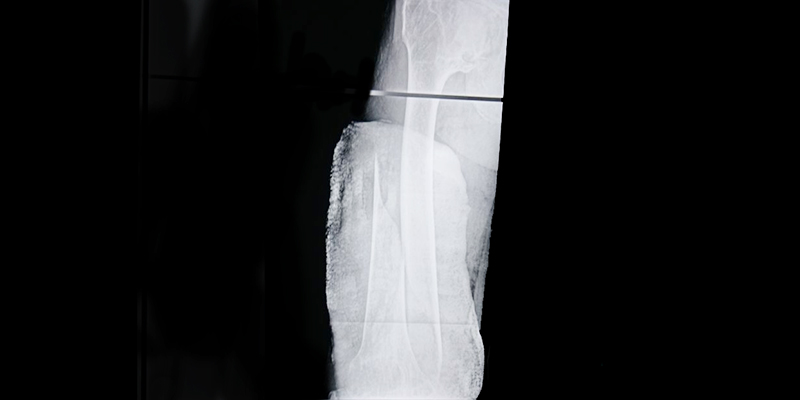

Закрытый перелом за две недели стал открытым

Как такое произошло? Одинокий мужчина 57 лет, возвращаясь домой в состоянии «подшофе», упал на лестничной клетке. Причем упал очень неудачно. Соседи занесли его домой, водрузили на кровать и ушли. День проходит - нога болит, два проходит - нога болит… Через две недели, когда у мужчины уже произошла перфорация кожи, и обломок кости вышел наружу сантиметра на четыре, соседи вызвали скорую. Так пациент оказался в Ивантеевском филиале Московской областной больницы имени профессора Розанова В.Н.

«Привезли его, конечно, не в самом хорошем состоянии, - говорит заведующий травматологическим отделением Геннадий Гаврилович Гордеев. - Из закрытого он получил открытый перелом бедренной кости. Причем все это время (две недели!) мужчина находился без повязок, уже образовавшуюся рану ничем не обрабатывал, что привело к нагноению околопереломной гематомы. Первоначально пациент был госпитализирован в хирургическое отделение, где была предпринята попытка одномоментной репозиции перелома с наложением гипсовой полу-кокситной иммобилизации. Однако, ввиду состояния больного, гипсовую фиксацию заменили скелетным вытяжением на шине Белера. Попутно проводилось лечение нагноившейся раны и гематомы. Потом пациент переведен в травматологическое отделение».

Здесь первым делом перелом был стабилизирован и зафиксирован, а далее продолжено лечение открытой раны в месте перелома. Проходило все, как говорят врачи, довольно спокойно и уверенно, без каких-либо дополнительных вспышек инфекционно-гнойного процесса. Сейчас пациент выписан и находится на амбулаторном наблюдении.

«К сожалению, сказать, что достигнут прекрасный результат, и мы выписали пациента таким, как он был до перелома, не можем, - признается Геннадий Гаврилович. - Честно говоря, не привыкли, чтобы из стен нашего травматологического отделения выходили пациенты с такой картиной, но клиническая ситуация диктует свои условия. Сейчас у пациента укорочение конечности, но провести реконструктивную операцию (погружной остиосинтез) будет возможно лишь через полгода-год - по всем канонам при наличии воспалительно-гнойного процесса раньше это сделать невозможно. Но пациент не останется без внимания, и, спустя положенное время, мы будем готовы вновь ему помочь».